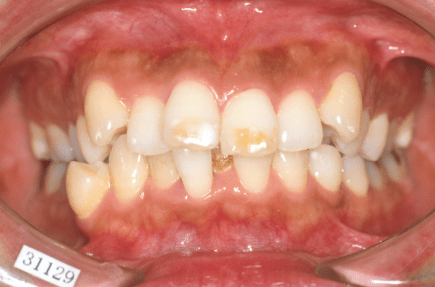

叢生(デコボコ)

原因:歯の大きさと顎の骨の横幅のアンバランス